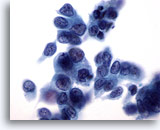

Figure 55

Breast FNA, Medullary carcinoma.

This cluster of cells shows large central nucleoli and abnormal chromatin. Lymphocytes are also noted. 60x

Figure 55

Breast FNA, Medullary carcinoma.

This cluster of cells shows large central nucleoli and abnormal chromatin. Lymphocytes are also noted.

60x